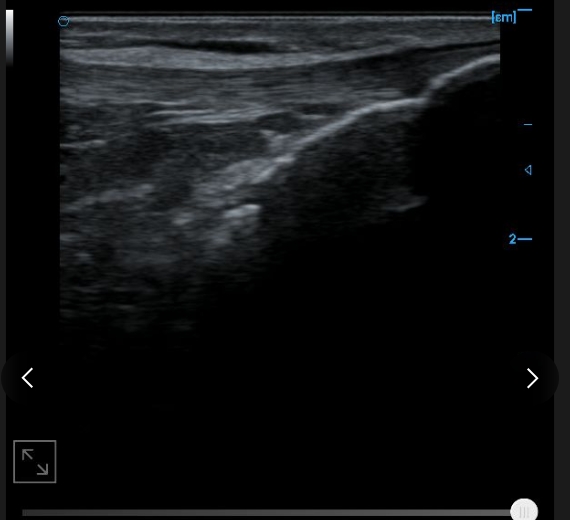

Patellar tendon B image